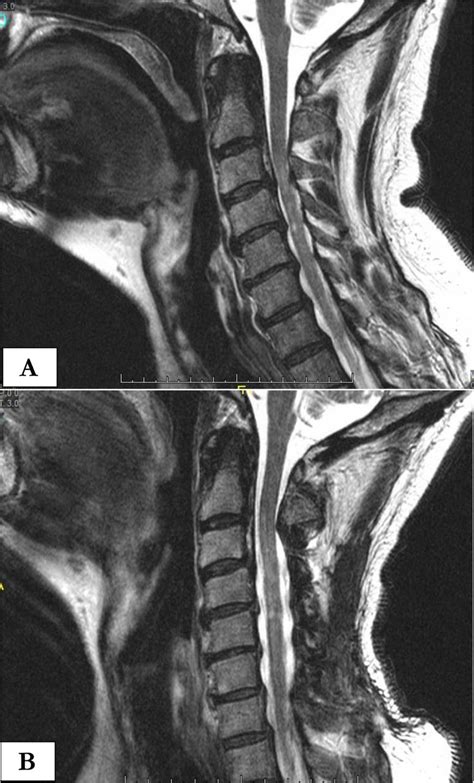

Preoperative T2-weighted sagittal magnetic resonance imaging clearly ...